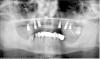

Брат 2 Опубликовано 27 июня, 2013 Автор Поделиться Опубликовано 27 июня, 2013 Идентичный случай. Бюджетный план.Позиция имплантатов 3.5 3.7 . Промежуточные касательно, промывные 0.5. Снимок пообещал принести через пару недель. Ссылка на комментарий

Wasja Опубликовано 27 июня, 2013 Поделиться Опубликовано 27 июня, 2013 Установил по 4 имплантата в позиции 3.4 , 3.6 , 4.4 , 4.6 . Кость широкая, плотная, по высоте свобода. Торк 50. Безлоскутно. Все имплантаты Select 4.3*13. Погрузил на 1 мм. Поставил формирователи. Снял оттиски. Через три дня одел постоянную конструкцию. Работает год. Никаких отличий. Интересует мнение профессионалов по данной тактике в кости малой плотности.На костной ткани малой плотности сразу нагружать не стоит.Снимок не совсем в тему. Удалил 7 зубов верх фронт, 4 имплантата с одномоментной установкой и немедленной нагрузкой на временных коронках+2 синуса. Ссылка на комментарий

Wasja Опубликовано 27 июня, 2013 Поделиться Опубликовано 27 июня, 2013 Сори, не тот снимок. 1 Ссылка на комментарий